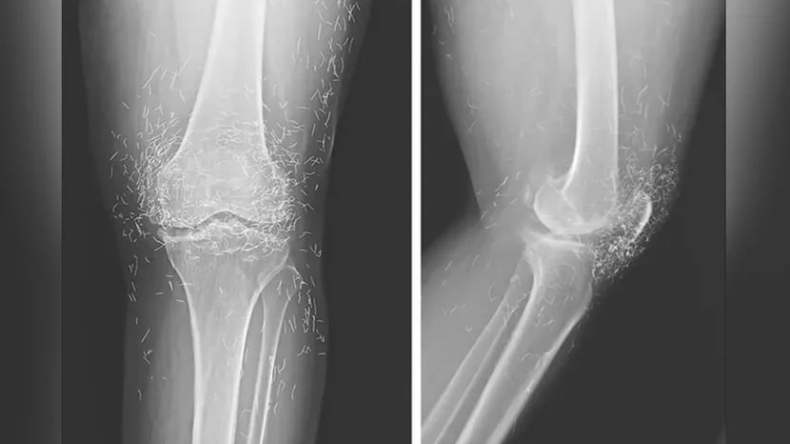

اكتشف الأطباء في كوريا الجنوبية أثناء علاج امرأة مصابة بهشاشة العظام في الركبة، مئات الخيوط الذهبية الخالصة مزروعة في ساقيها، الأمر الذي أثار استغرابهم.

في النهاية، اشتد ألم ركبتيها لدرجة أنها اضطرت للعودة إلى المستشفى، فكشف فحص الأشعة السينية عن سماكة وتصلب في الجزء الداخلي من عظمة الساق، ونمو عظمي في الركبة، وجميعها أعراض شائعة لهشاشة العظام.

بالإضافة إلى مئات الخيوط الذهبية الدقيقة المغرزة في الأنسجة المحيطة بالركبة.